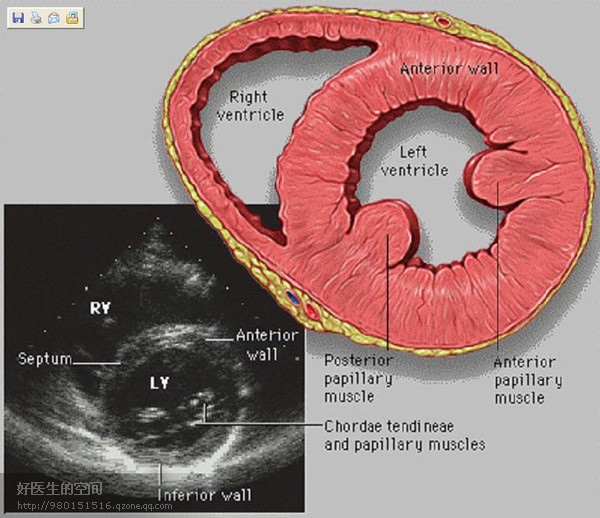

经典心脏超声切面图及解剖标示